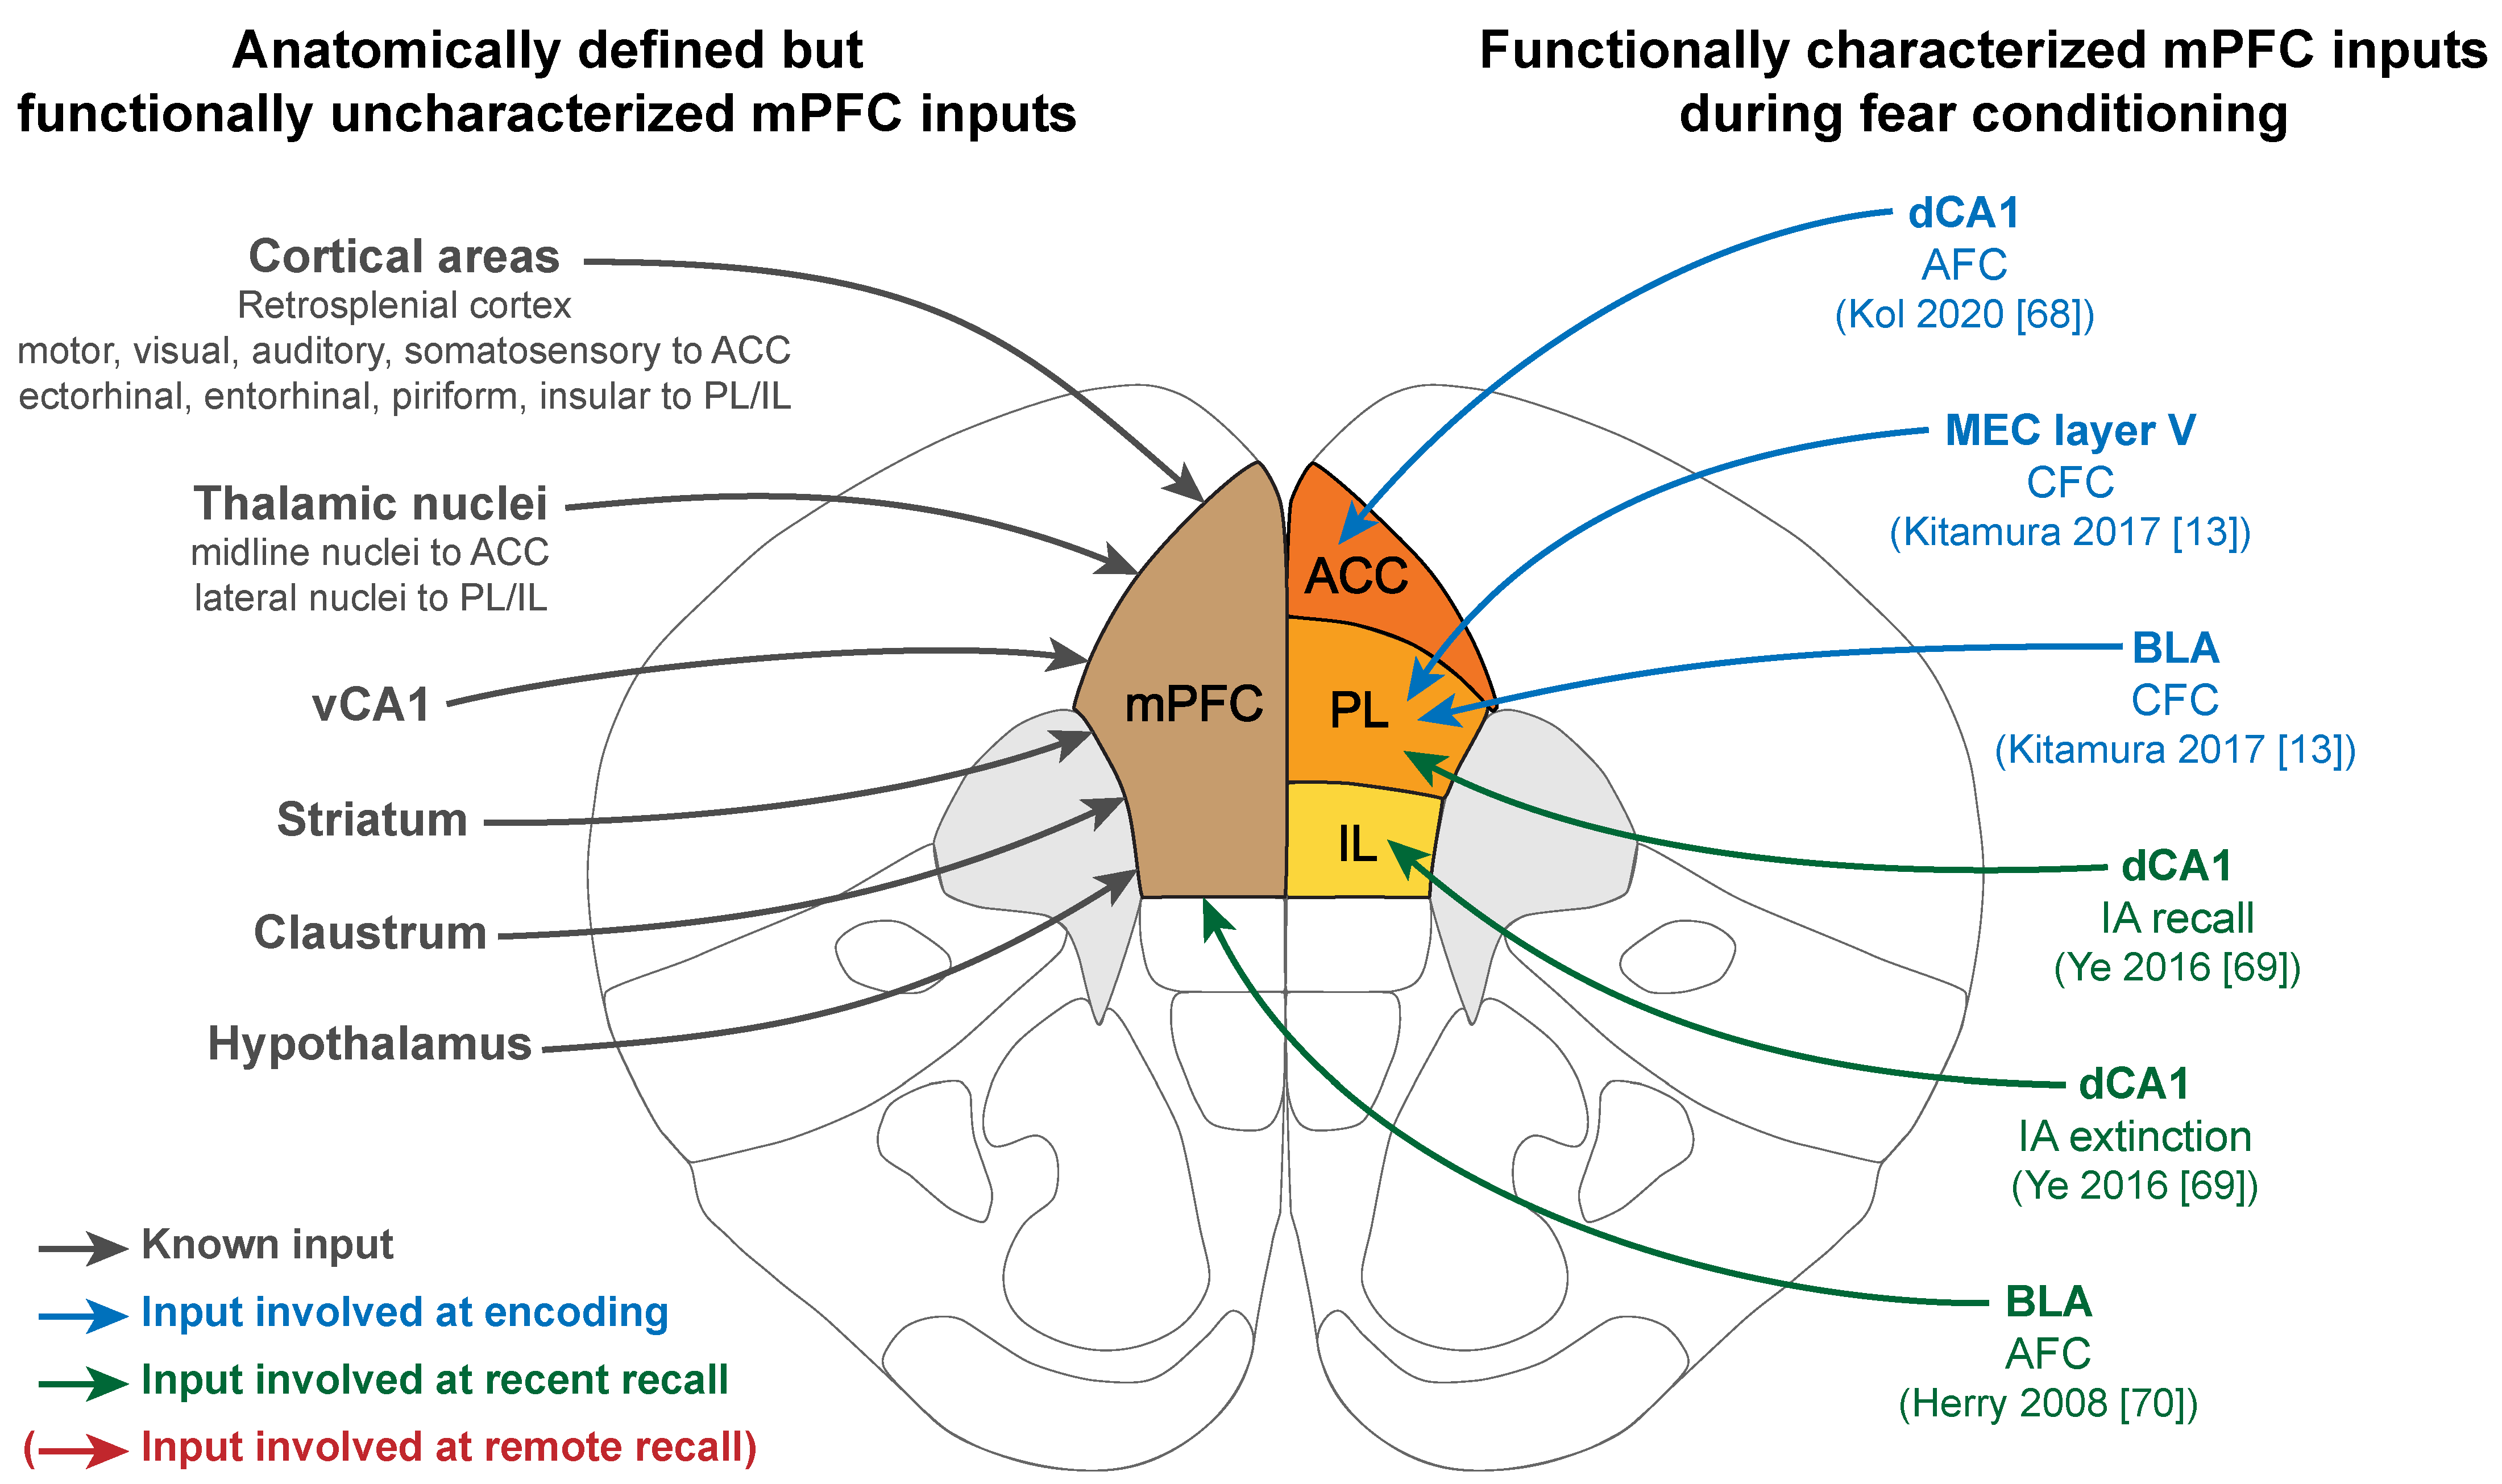

L'Épée / MB&F Arachnophobia Clock – Tomini Classics。Zildjian FX Stack 10 in. | Guitar Center。Literature Review] MARCA: Mamba Accelerator with。The Medial Prefrontal Cortex and Fear Memory: Dynamics。間のか楔 AMBIVALENCE